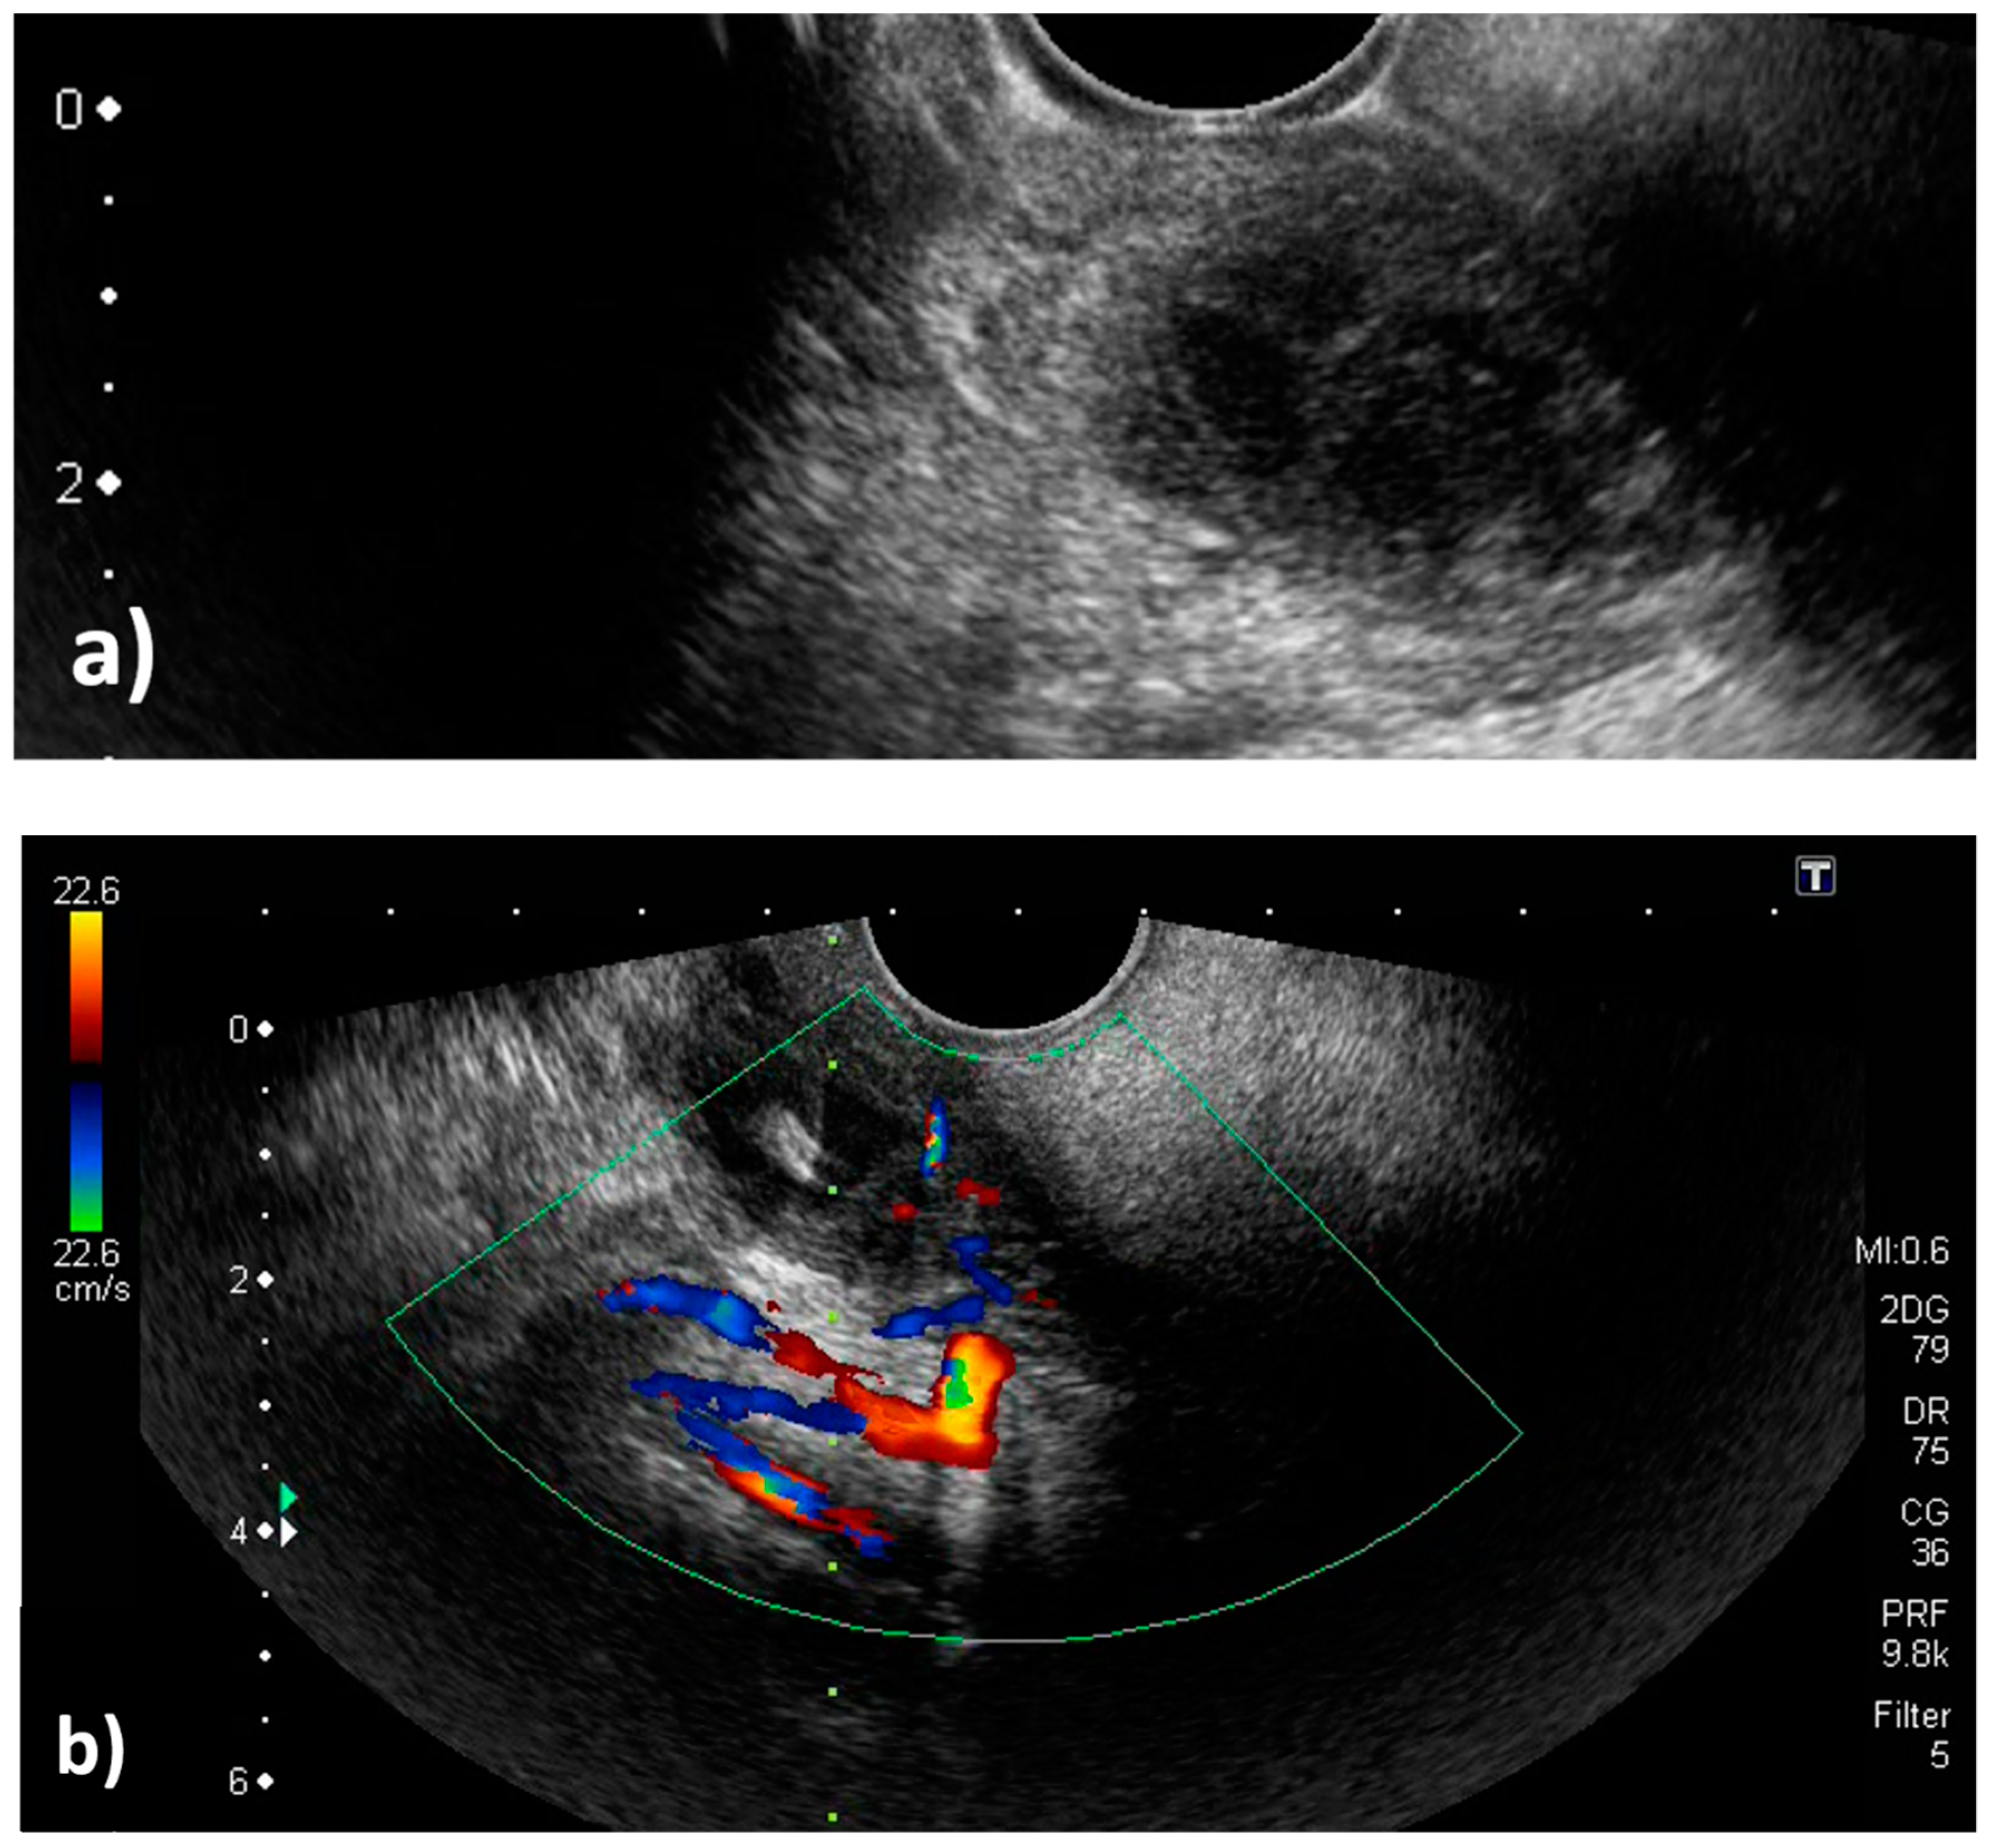

2. Case Report